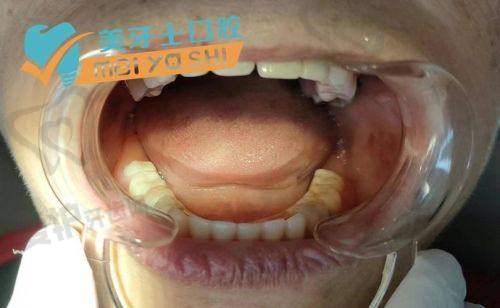

这个价格起的半口牙种植项目,包含了一系列的服务内容。首先是全方面的口腔检查。在种植手术前,贾医生会为患者进行详细的口腔检查,包括口腔X光片、CT扫描等,以正确了解患者的牙槽骨情况、牙齿缺失情况以及口腔健康状况。这一步骤非常重要,它为后续制定种植方案提供了科学依据。其次是个性化的种植方案设计。贾医生会根据检查结果,结合患者的需求和期望,设计出更适合患者的半口牙种植方案。方案中会确定种植体的品牌、型号、数量以及种植的位置等。再者就是种植手术的费用。手术过程中,贾医生会凭借不错的技术,将种植体正确地植入患者的牙槽骨内。手术采用精良的麻醉技术,确保患者在手术过程中不会感到明显的疼痛。此外,还包含术后的护理和随访服务。医院会为患者提供详细的术后护理指导,帮助患者更好地修复。同时,会定期对患者进行随访,了解种植体的愈合情况和患者的口腔健康状况。

天津蓟州京医口腔医院贾岩半口牙种植35000元起,这里的“起”字意味着价格会根据不同的情况有所变化。种植体品牌不同价格有差异。市场上有多种种植体品牌可供选择,如欧美品牌、韩国品牌等。欧美品牌的种植体通常质量和性能较好,但价格相对较高,半口牙种植的费用可能在50000 - 80000元左右。韩国品牌的种植体性价比相对较高,半口牙种植价格可能在35000 - 50000元之间。患者的口腔情况也会影响价格。如果患者的牙槽骨条件较好,不需要进行额外的骨增量手术,那么种植费用相对较低。但如果患者的牙槽骨条件较差,需要进行骨增量手术、上颌窦提升等复杂操作,那么费用就会相应增加,可能会达到80000元以上。修复材料的选择也会导致价格不同。种植体植入后,需要安装牙冠等修复材料。不同材质的牙冠价格也有所不同,如全瓷牙冠相对美观、耐用,但价格较高,会使整体的半口牙种植费用有所上升。需要注意的是,以上价格仅供参考,具体的费用还需要根据患者的实际情况,由贾医生进行评估后确定。